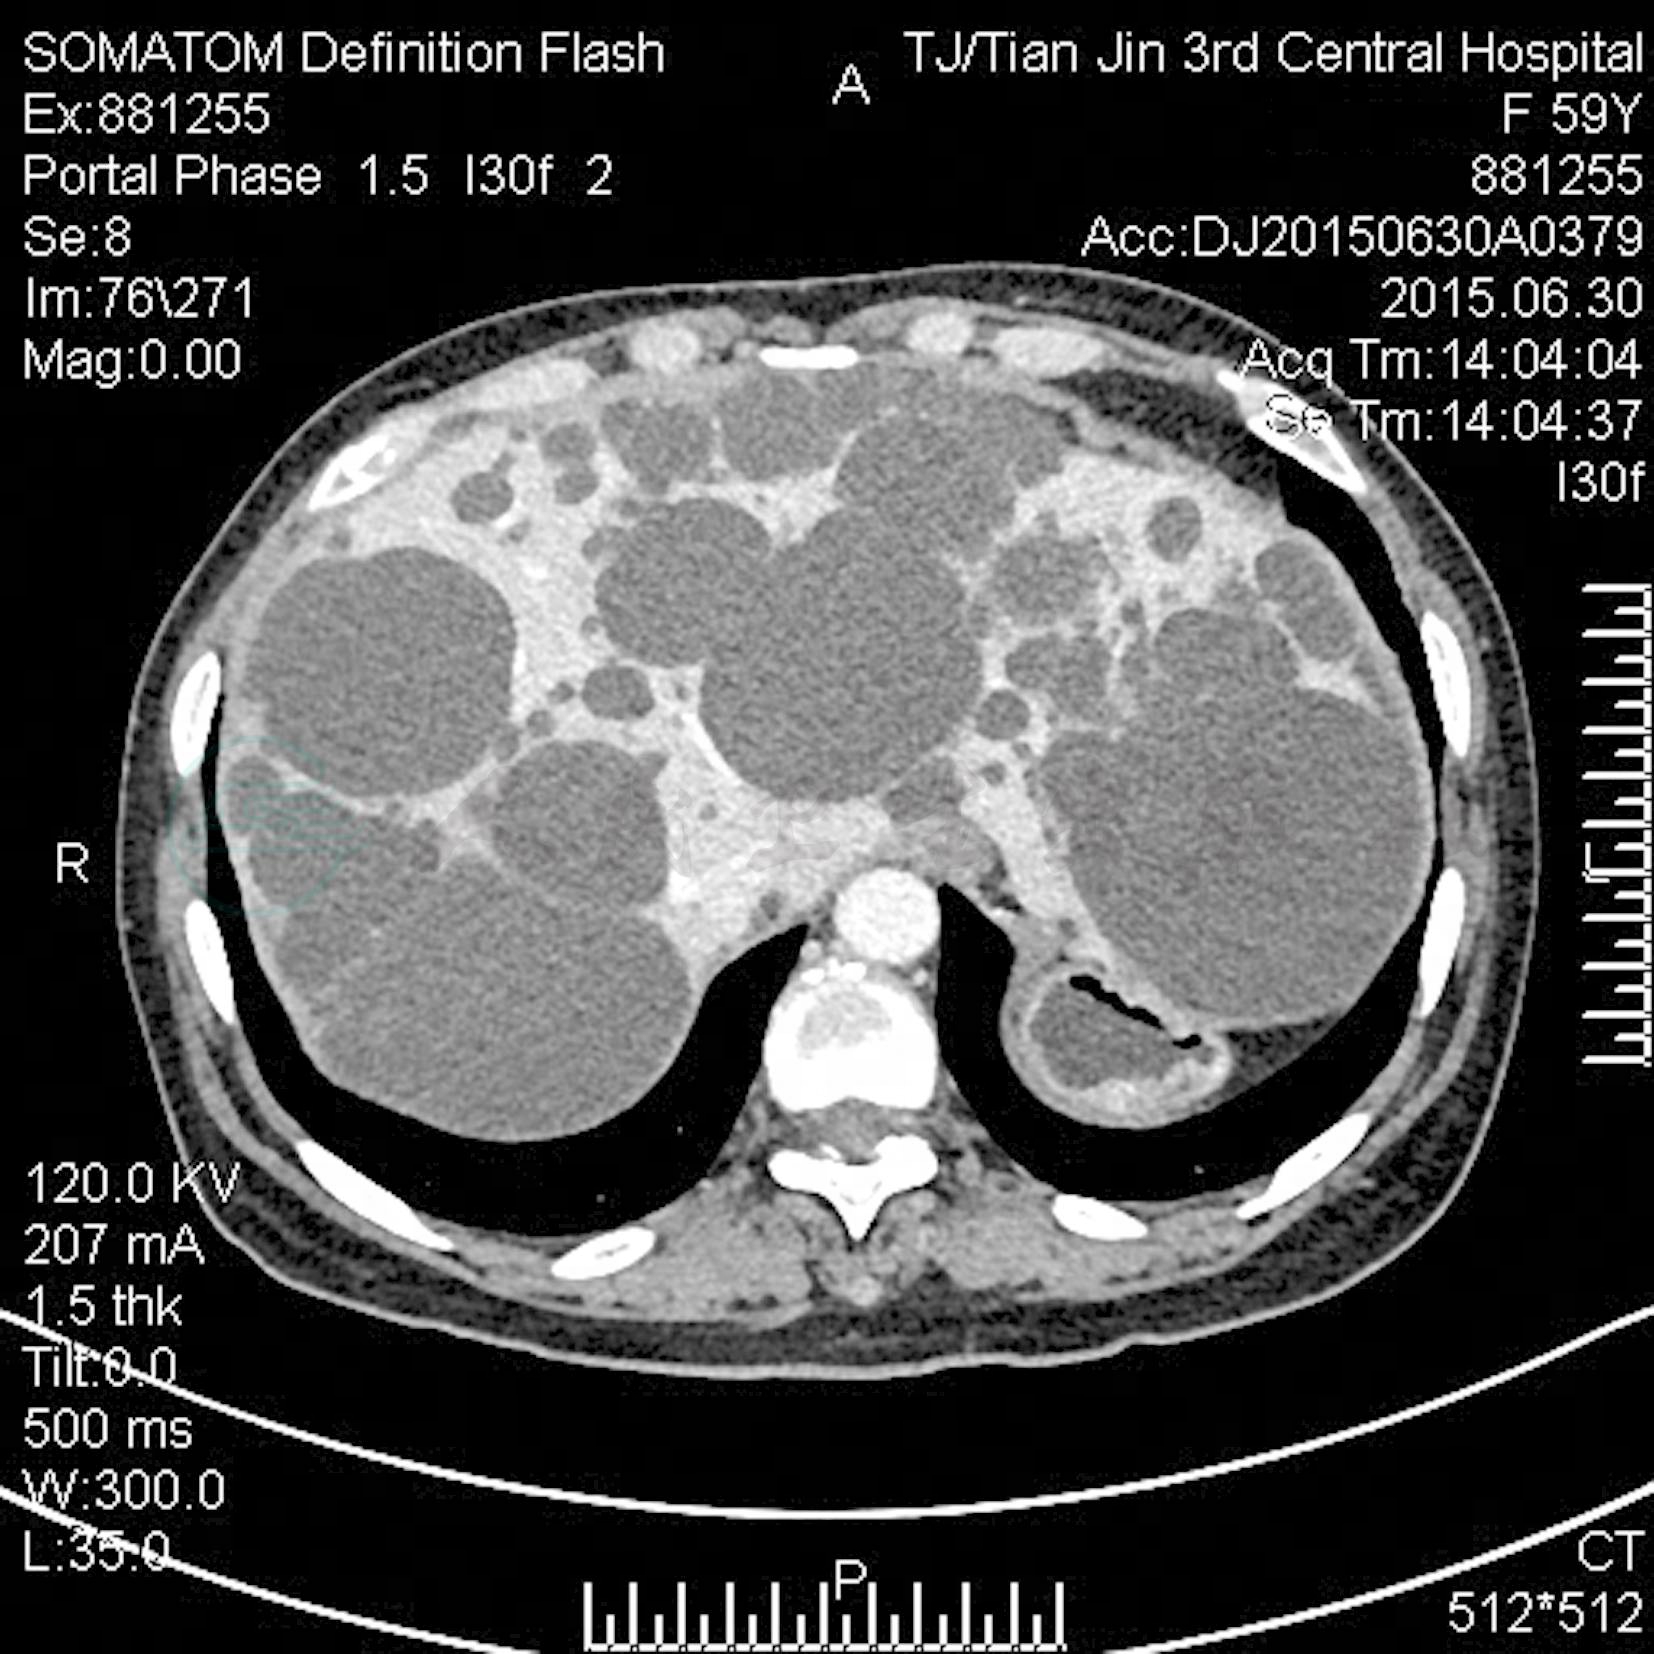

Gigot等于1997年提出根据CT扫描所显示的肝内囊肿数目、大小及剩余肝实质量将多囊肝分为以下3型:Ⅰ型是指肝内有数目<10个的大囊肿 (直径>10cm);Ⅱ型是指肝内弥漫分布多发、中等大小的囊肿,数目>10个,但还剩余较多量正常的肝实质;Ⅲ型是指肝内弥漫分布多发、小至中等大小的囊肿,且仅剩余少量正常的肝实质。

B型超声波和CT检查可见到肝内有无数大小不等的囊肿 (图1),囊肿彼此相连,多呈簇状分布,多房融合成分隔,之间多无正常肝组织,囊肿所占肝体积50%以上。

图1 多囊肝CT门静脉期